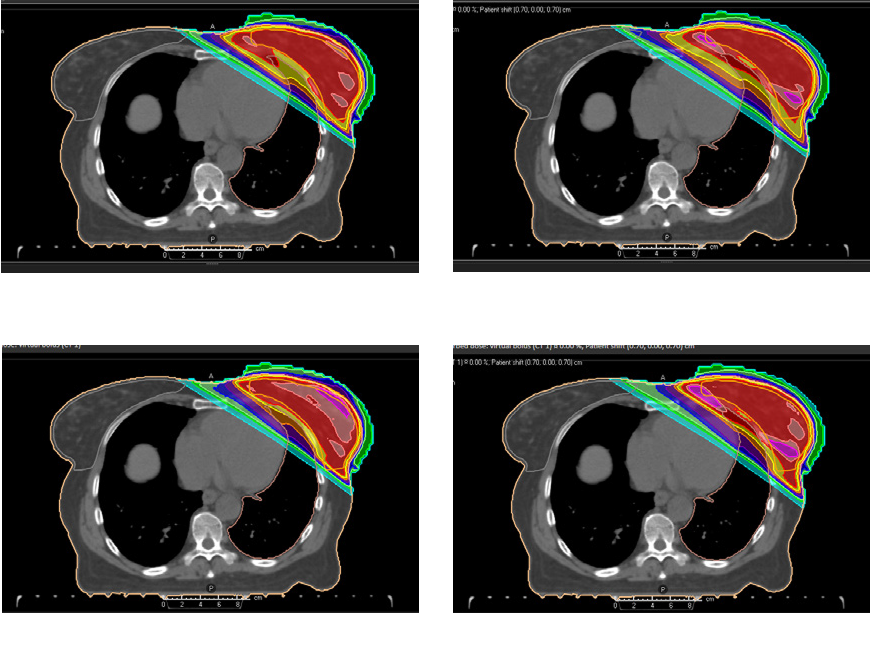

Example 1 (Figure 2)

Robust optimization for IMPT applied to a 4D-CT lung case subject to at most 0.5 cm setup errors and 3.0 % density errors was compared to margin-based planning. The ten phases of the 4D-CT were included in the robust optimization. Transversal slices of the planning CT (CT 1) under the nominal scenario and of a non-planning CT (CT 6) under a perturbed scenario are shown in Figure 2. The figure illustrates that robust optimization can lead to improved robustness at the same time as decreased integral dose compared to conventional margins.

Figure 2